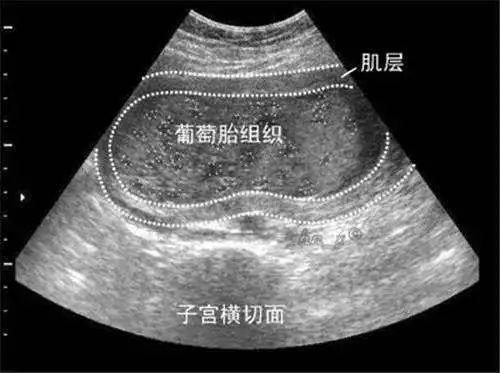

葡萄胎是指妊娠后胎盘绒毛滋养细胞增生,间质高度水肿,形成大小不一的水泡,水泡间相连成串,形如葡萄,亦称水泡状胎块。

葡萄胎是指怀孕后滋养细胞不规则增生、绒毛间质水肿,每一个水泡,就是一根水肿的绒毛,许多水泡连在一起,看上去就像一串串葡萄,因而称之为葡萄胎。

葡萄胎一般在怀孕40~50天左右到医院做B超就可以发现,停经后阴道流血是葡萄胎最早和最常见的症状,发生率一般在98%以上。